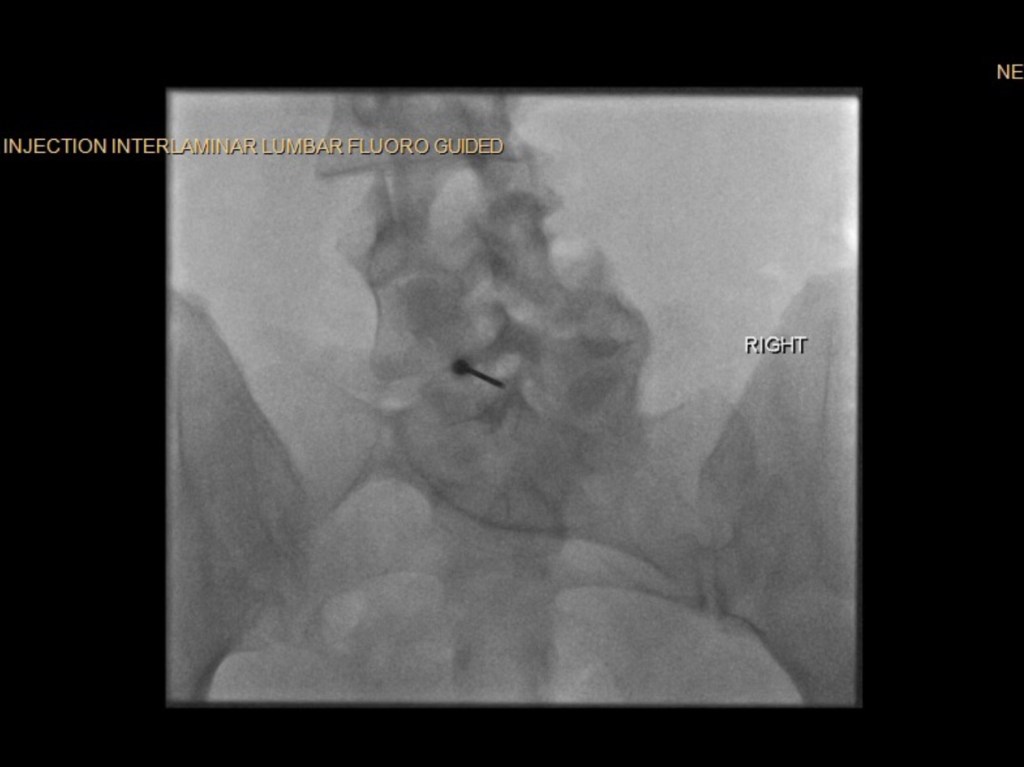

At my 3-month post-op appointment, my surgeon lifted all my restrictions and said I can return to all activity, “just listen to [my] body.” She measured my X-rays (above) and said my lumbar curve decreased 20 degrees, and the thoracic is the same. Also, I grew half an inch. I showed her the scoliosis program I found in New Hampshire, and she was all for it. I’ve booked a furnished apartment in New Hampshire 4/20-5/31 and scheduled the 12 sessions of treatment at the PT clinic there. I’m hopeful that will help with my back pain, and maybe even reduce my thoracic curve. And right before that, I’ll be attending Bionicon!